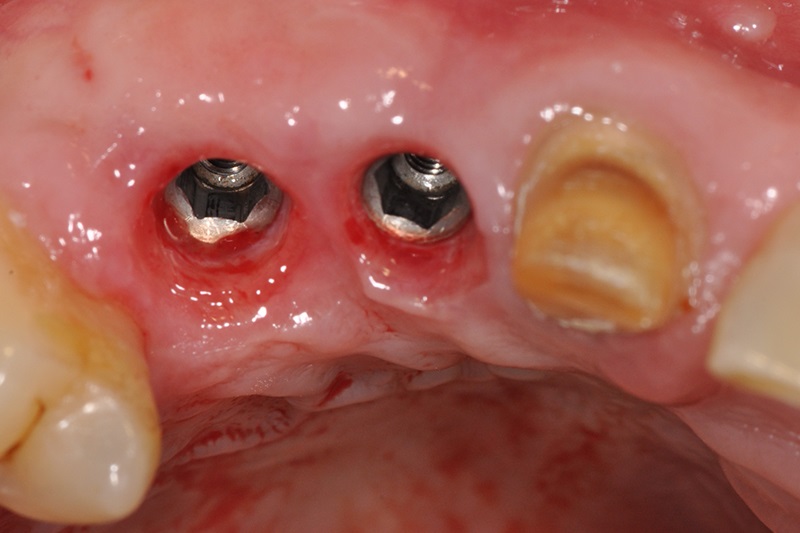

缺牙多顆

案例一

術中